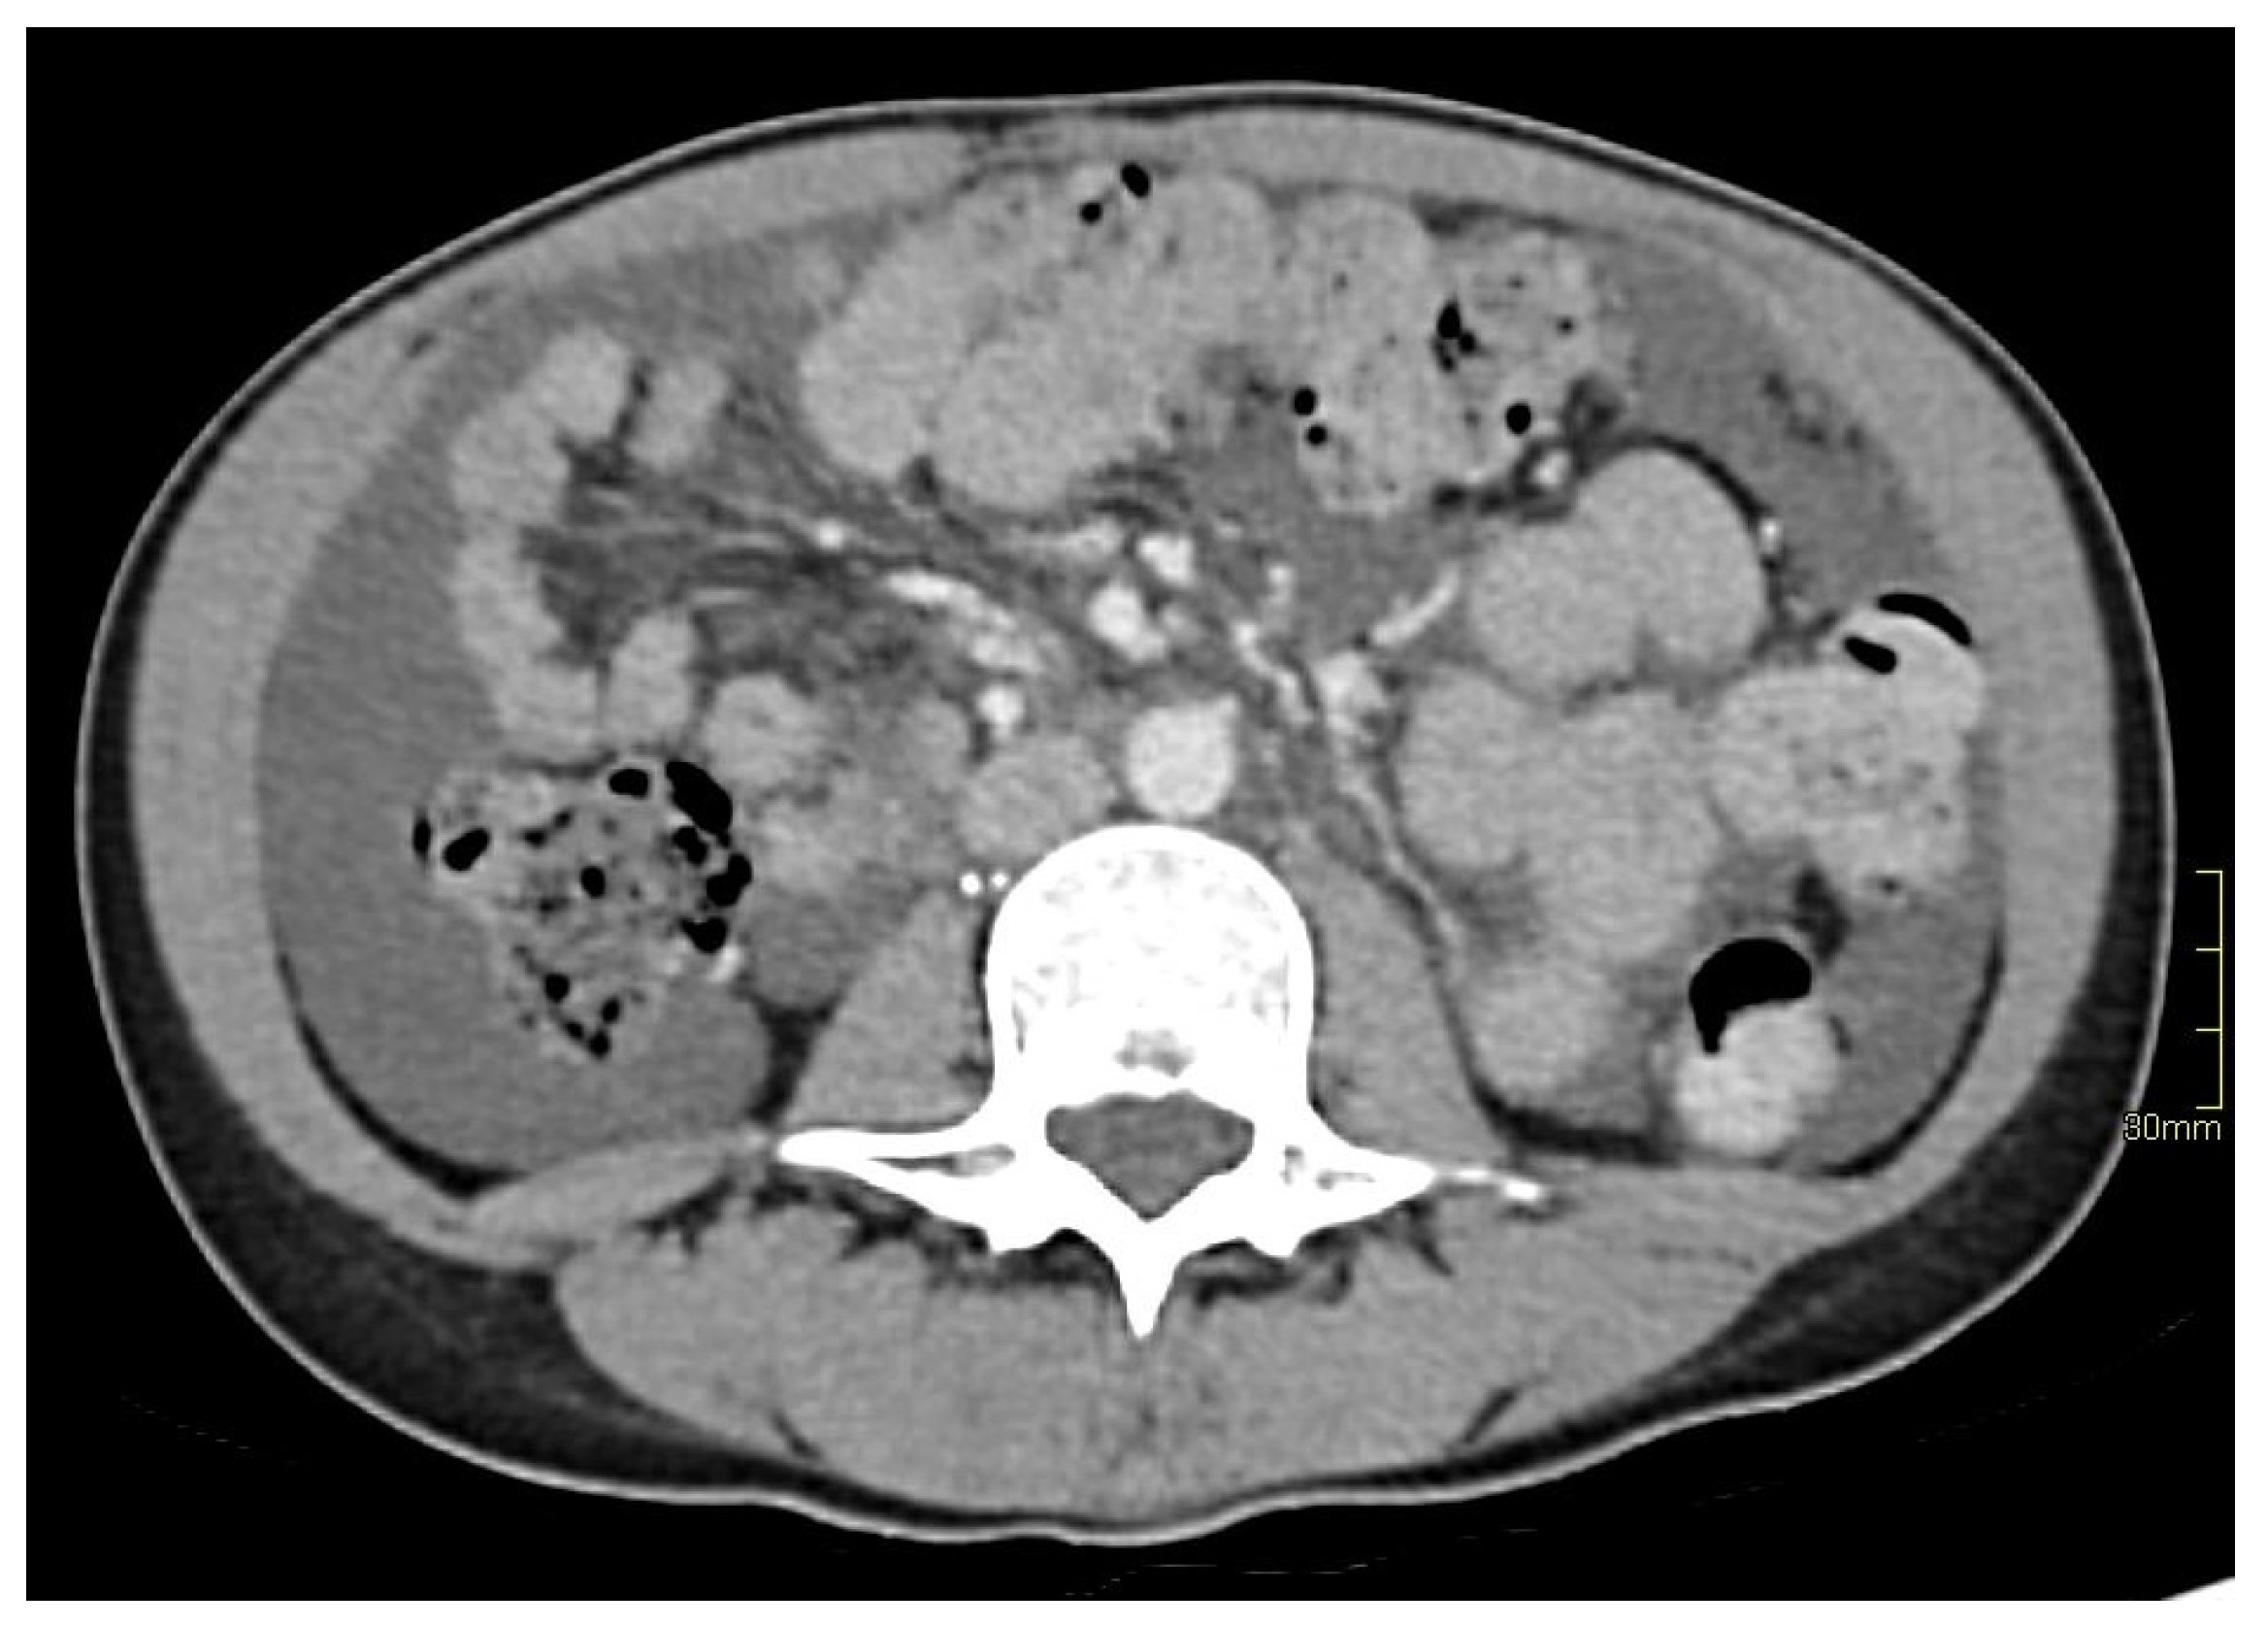

2. Case Report

3.1. Case Discussion and Physiopathological Hypothesis